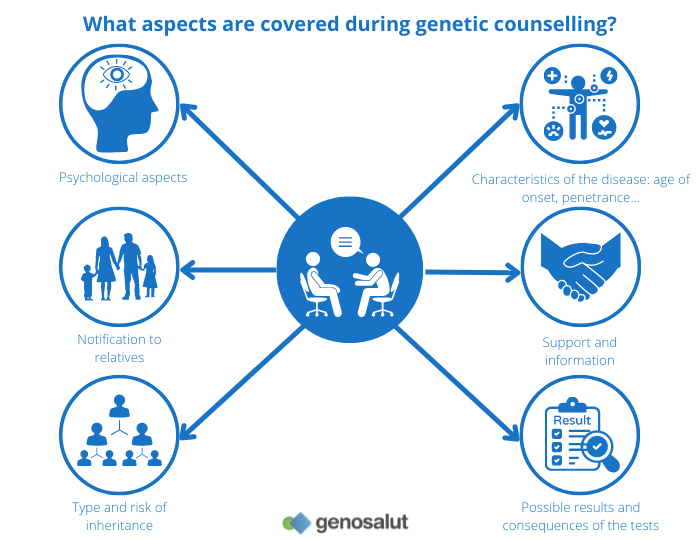

Expert genetic evaluation and counseling for inherited and complex cardiac conditions, supporting families with accurate diagnosis, guidance, and long-term care planning.

Genetics / Cardiac Genetics

Expert genetic evaluation and counseling for inherited and complex cardiac conditions, supporting families with accurate diagnosis, guidance, and long-term care planning.